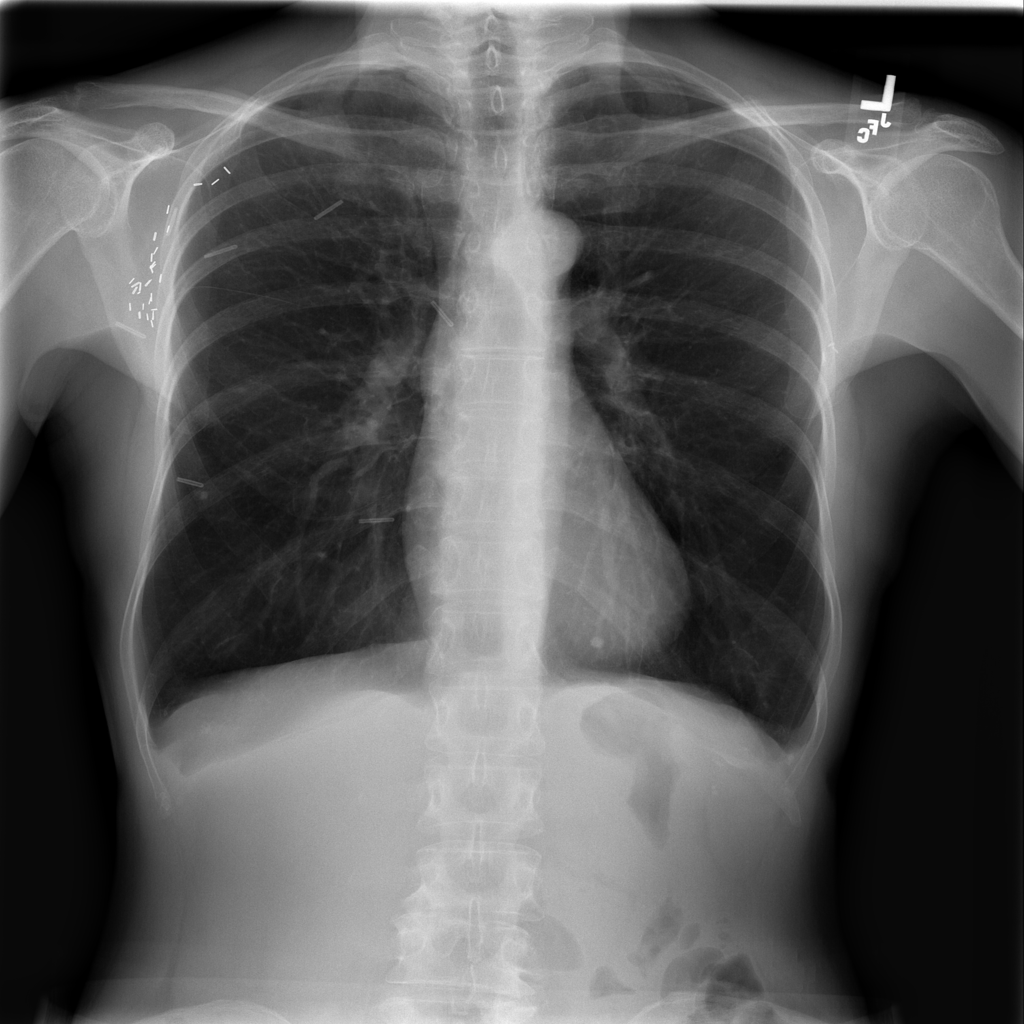

PAT-C255 · IMG-000Emphysema

PAT-C255 · IMG-000

PA